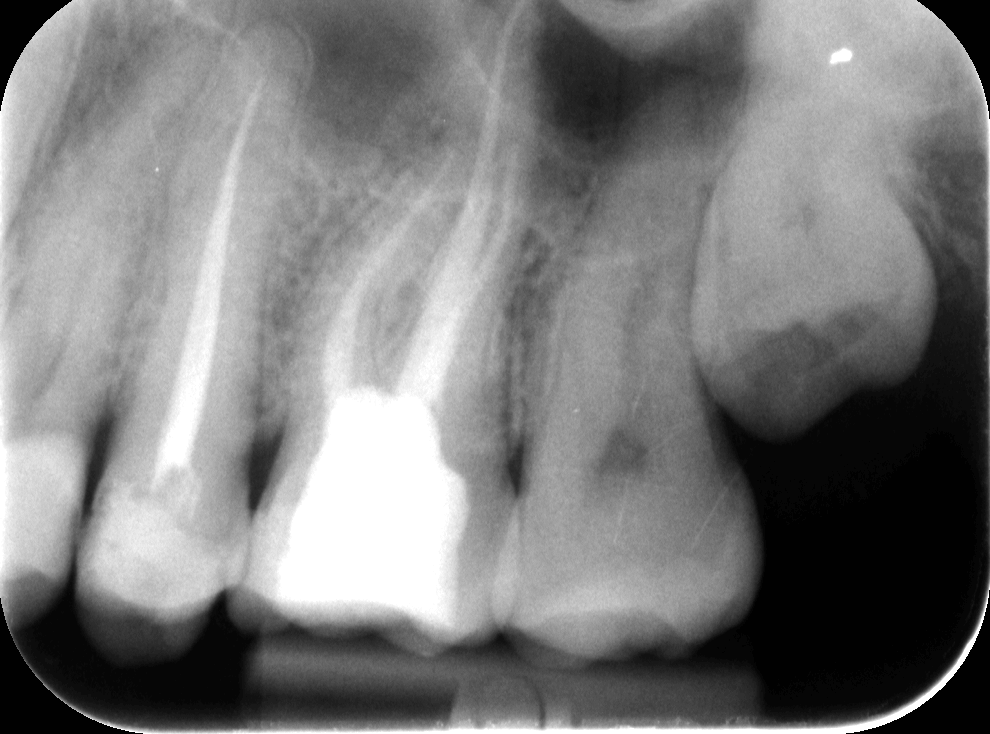

Dr. Molnár Katalin, egyik szakértőnk vizsgálta meg a pácienst. A szájüregi vizsgálatot röntgenfelvétel követte – a diagnózis felállításához és a kezelés menetének felvázolásához mindenképpen szükség van röntgenfelvételre is. A képen látható, hogy egy rosszul elvégzett gyökértömés van az egyik felső 6-osban, amely körül már látható a kezdődő elváltozás. A rossz gyökértömés körül ugyanis könnyen gyulladás alakul ki, amely nemcsak fájdalmas, de meg is változtatja a csontszövet szerkezetét.

Dr. Molnár Katalin mikroszkópos berendezéssel szakszerűen elvégezte a fogtömés cseréjét. Ezen a képen ugyanaz a fog látható már a gyökértöméscsere után. Megfigyelhető, hogy a sötét területek kivilágosodtak. Ez arra utal, hogy a gyulladás gyakorlatilag megszűnt, a fog gyógyultnak tekinthető.